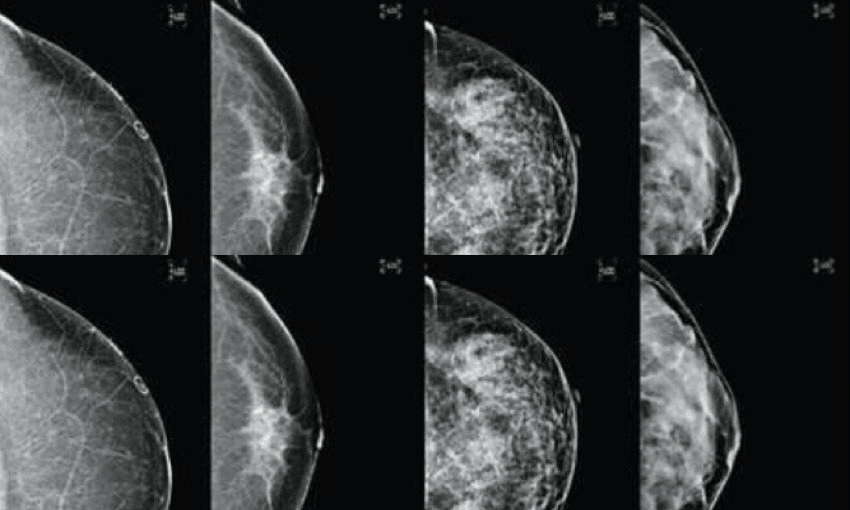

Emily Writes’ interview with Dr Monica Saini explains the role of mammograms in screening. Here is the broader process that screening mammography fits into: Women are first invited for a mammogram as part of the free breast cancer screening programme for women aged 45 to 60. If the mammogram shows something of concern, women are recalled and have to be seen within two weeks. There is a comprehensive work up including radiology, pathology and a meeting with a surgeon – all of which takes place on the same day. Results must be returned within seven days, and a treatment plan agreed upon once the results are available. Treatment should have commenced within four weeks of results being shared with the patient. Penalties apply for DHBs who do not meet these targets. Dr Ronald says this comprehensive, wraparound service with strict targets is a big part of what makes the screening programme so successful.